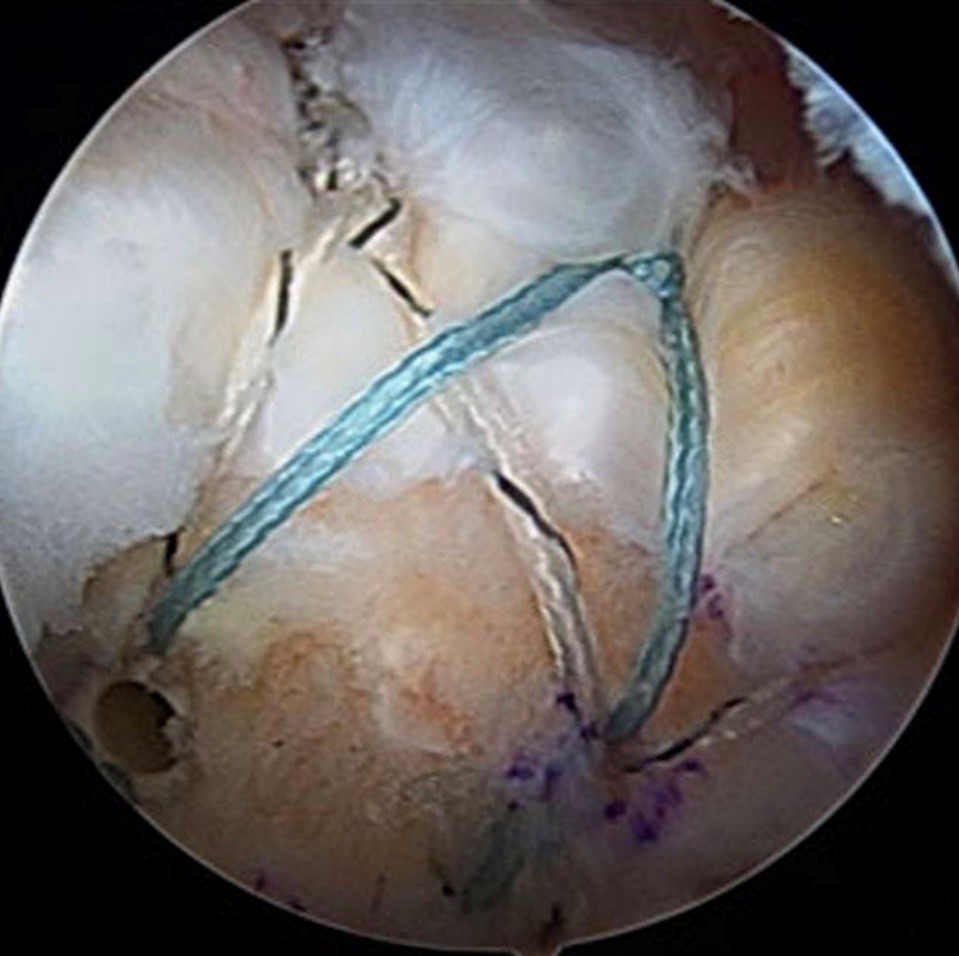

Sau hội chẩn chuyên môn, các bác sĩ chỉ định phẫu thuật nội soi khớp vai khâu gân bằng kỹ thuật Double-Row (kỹ thuật khâu hai hàng): cắt lọc tổn thương, tạo hình khoang dưới mỏm cùng vai và khâu phục hồi gân chóp xoay.

BSCKII. Ngô Hải Quang – Phó giám đốc Trung tâm Chấn thương Chỉnh hình – Bỏng cho biết: kỹ thuật Double-Row (khâu hai hàng) là kỹ thuật mới được áp dụng tại Việt Nam trong những năm gần đây. So với kỹ thuật Single-Row (khâu một hàng) trước đây, Double-Row có độ vững sinh học cao hơn, giúp tăng khả năng liền gân và phục hồi chức năng vai, đặc biệt hiệu quả trong những trường hợp rách lớn hoặc rách tái phát.